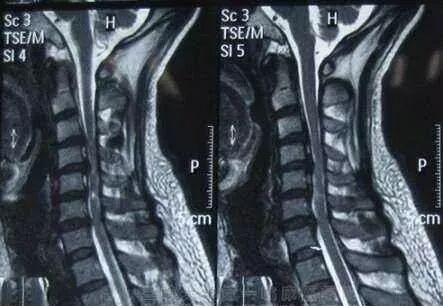

脊髓型颈椎病

髓型颈椎病的发病率占颈椎病的12-20%,也是目前许多骨科,和大夫非常头痛的一种颈椎病类型,因为他的影响十分严重。甚至可造成肢体瘫痪,脊髓型颈椎病致残率高。

脊髓型颈椎病通常起病缓慢,以40-60岁的中年人为多。脊髓型颈椎病的发病,和严重程度,往往和有无颈椎管狭窄有很大关系。

症状

1.多数患者首先出现一侧或双侧下肢麻木、沉重感,随后逐渐出现行走困难。上下楼梯时需要借力。严重者步态不稳、行走困难。患者双脚有踩棉感。

2.出现一侧或双侧上肢麻木、疼痛,双手无力、不灵活,像写字、系扣等精细动作难以完成。严重者甚至不能自己进食。

3.躯干部出现感觉异常,患者常感觉在胸腹部、或双下肢有如皮带样的捆绑感。同时下肢可有烧灼感、冰凉感。

4.部分患者出现排尿无力、尿频尿急、尿不尽、尿失禁或尿潴留等排尿障碍,大便密结等,性功能减退。